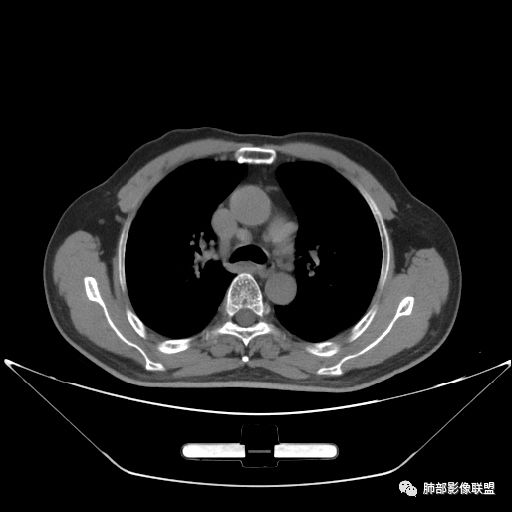

住院4天后行胸部增强CT

静脉期

老年男性,因“咳嗽咳痰1月余。”入院。病程中咳嗽咳痰,咳黄白痰,间断咯少许鲜红色痰血。PPD阳性。胸CT:右肺中叶外侧段支气管管腔阻塞,大片实性病变,病灶边缘光滑,部分边缘膨隆,可见分叶,肺门及纵隔可见肿大淋巴结,并可见钙化。增强可见病灶明显强化,而且延迟强化明显,病灶内多发低密度区,内见血管影,血管变细、部分血管破坏。考虑恶性病变可能性大,鉴别慢性肉芽肿性病变。

胸CT:跨叶大肿块,主体在中叶,右中叶外侧段支气管阻塞,病灶部分边缘膨隆,可见分叶,部分边缘平直,肺门及纵隔可见肿大淋巴结。增强病灶不均匀强化,延迟强化明显,病灶内多发低密度区,内见血管飘浮,部分血管变细、模糊。考虑:恶性病变可能性大,大细胞?淋巴瘤?鉴别慢性肉芽肿性病变。

吴婧老师和南边老师都对该病例进行了深入分析。从支气管管壁的增厚,支气管狭窄后扩张,支气管粘液栓,病灶形态,到病灶不均匀强化及坏死彻底,到周边病灶及肺组织空气的潴留,加之纵隔内淋巴结肿大伴钙化等等,都支持慢性炎性病灶,尤其是结核。

墨西哥仙人掌征---结核        影像上结核灶,粗大的均匀枝干,推测是支气管囊状扩张引起的,在非支气管区,形成圆形坏死囊群;如果这些坏死比较稀薄,又遇到扩张支气管,就会形成粗大的“墨西哥仙人掌”。结核引起的支气管近端炎症纤维化,可以造成支气管阻塞,从而将干酪样坏死物封堵在管腔内。仙人掌主干内部应该是干酪为主,稀薄的,具有流动性,时间久了会出现钙化。